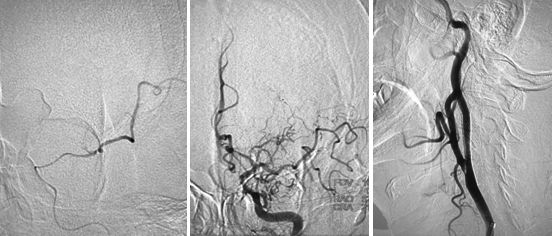

在路径途指导下,将微导丝(Transcend)、微导管(Rebar 027)沿导引导管送至左侧大脑中动脉M2段,撤出微导丝,经微导管造影,造影证实微导管位于真腔内,大脑中动脉远端血管通畅,将取栓支架Solitaire AB (6x30mm) 送至血栓处,释放取栓支架,静置5分钟后取出支架,可见支架内大量血栓,复查造影提示左侧大脑前动脉、左侧大脑中动下干通畅,左侧前大脑前动脉可向左侧大脑中动脉代偿供血,(图7)此时患者右侧肢体无力症状明显好转,仍有不完全混合性失语,观察10分钟后复查造影提示血流仍然通畅,颈动脉支架处血流通畅,遂结束手术,继予以替罗非班抗栓治疗。

图7

术后查体:神清,不完全混合性失语,右侧鼻唇沟浅,伸舌右偏,右侧肢体肌力4级,左侧肢体肌力5级,右侧针刺觉减退,右侧巴氏征阳性。NIHSS评分:4分。

术后复查头颅平扫CT可见左侧基底节区局部造影剂滞留(图8)